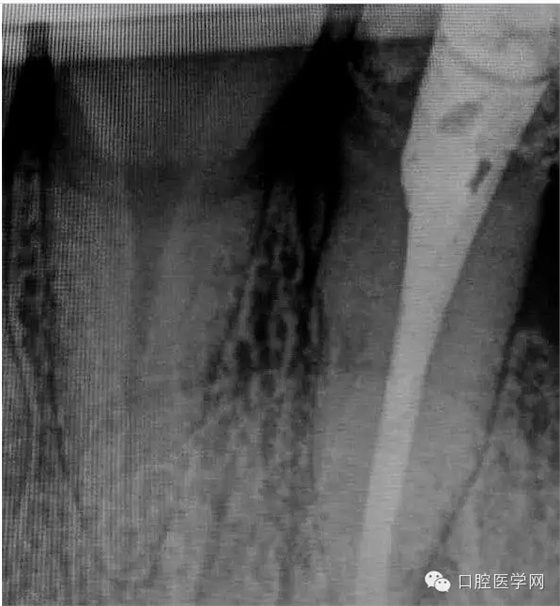

4.準(zhǔn)備放置橡皮障(由于拍片是較遠(yuǎn),所以,橡皮章暫時(shí)取下),去除暫封材料。在顯微鏡放大視野中,蔣調(diào)拌好MTA輸送至根尖部。

5.待MTA凝固后進(jìn)行熱牙膠充填。